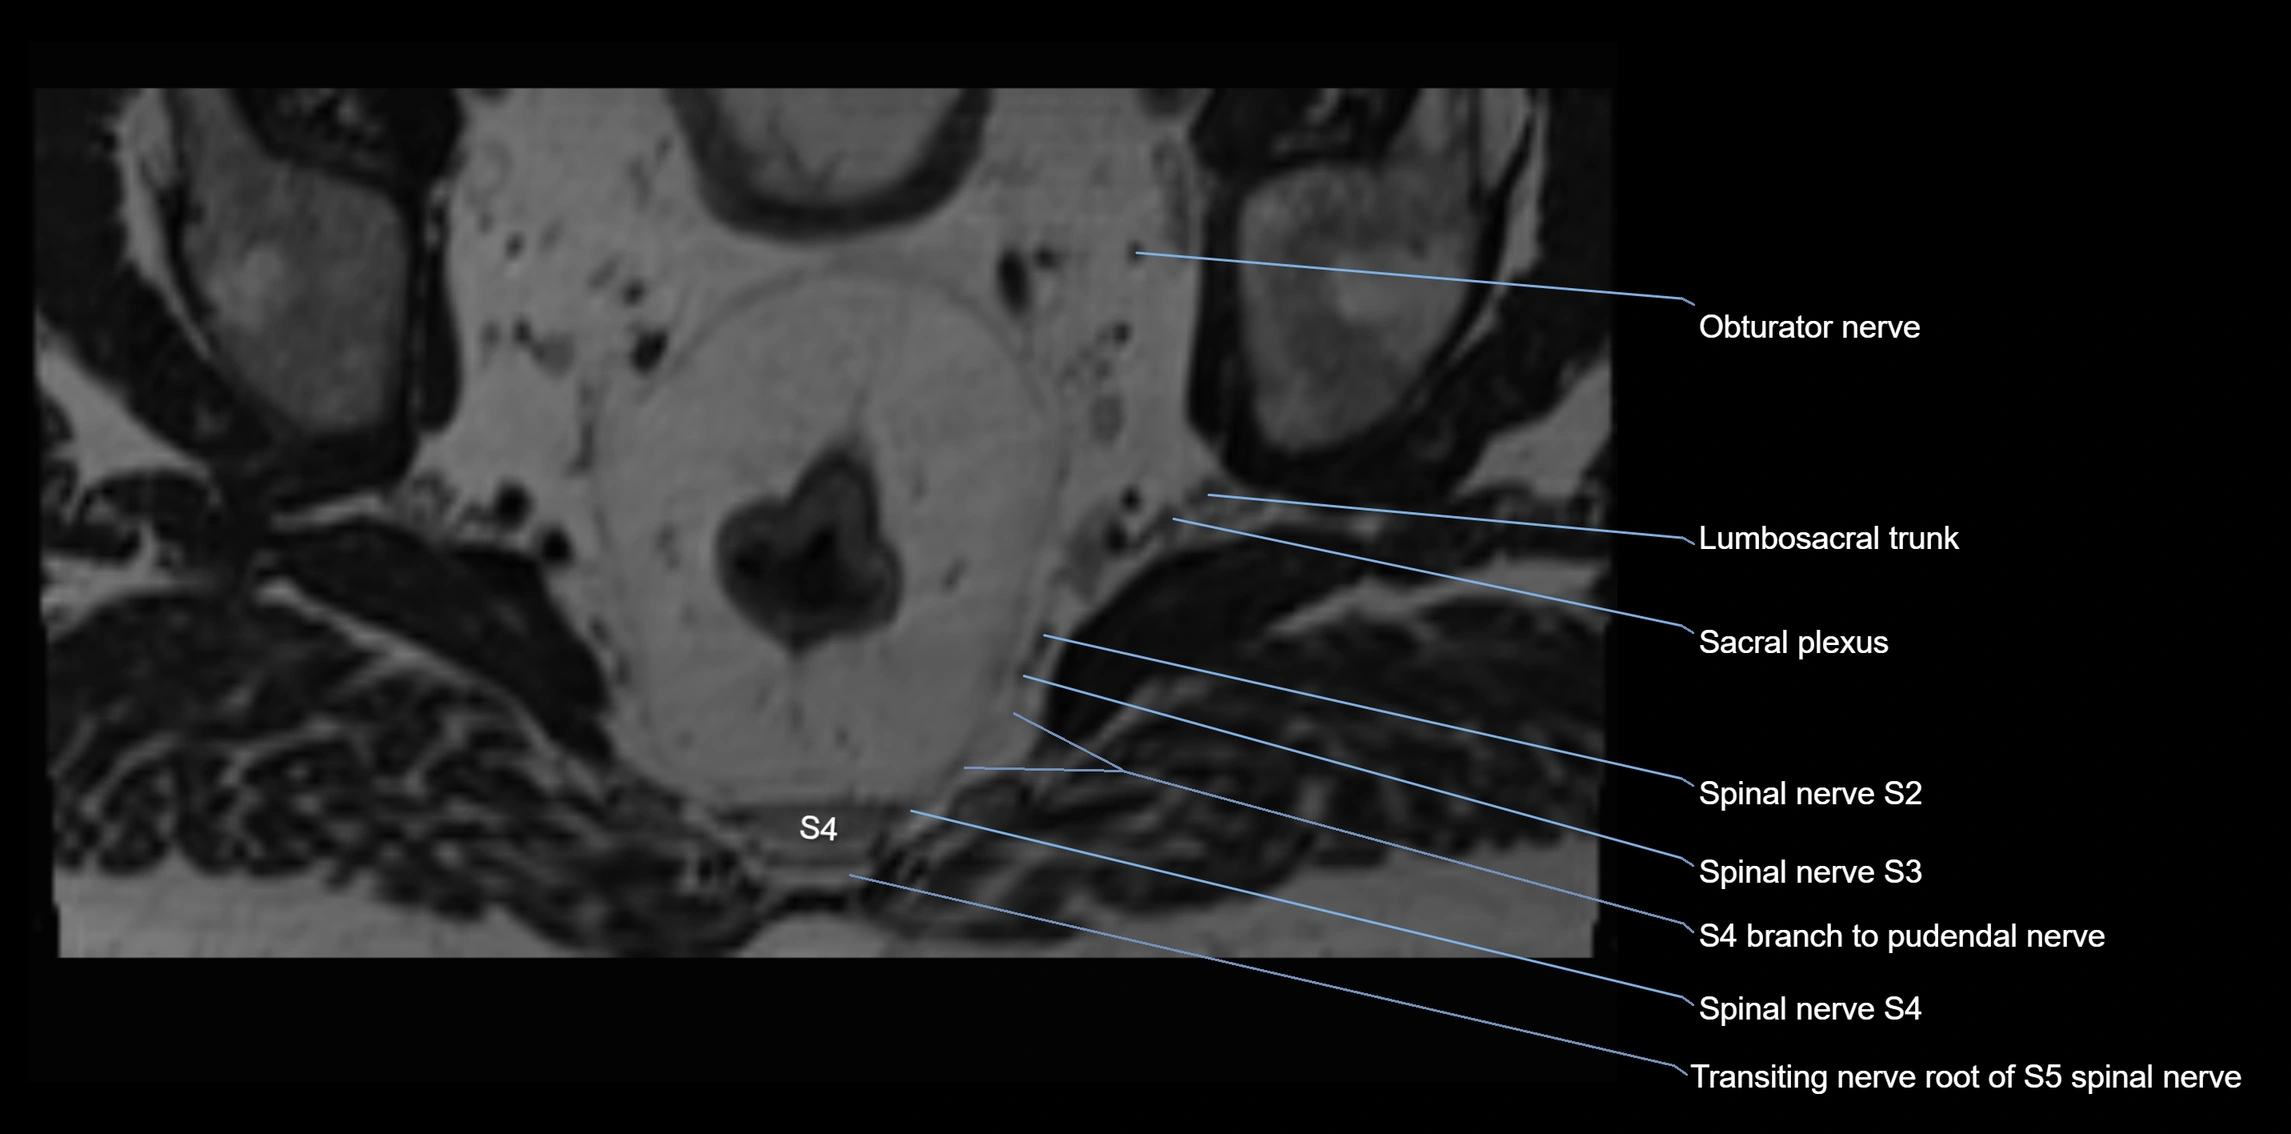

MRI image

image